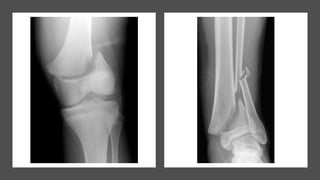

• This fracture pattern is frequent around the

medial malleolus ,lateral condyle of humerus.

• In type 4, treatment principles

include obtaining anatomic

reduction and adequate

stabilization to restore the

articular surface and prevent

metaphyseal–epiphyseal cross

union , to prevent subsequent

growth disturbances.